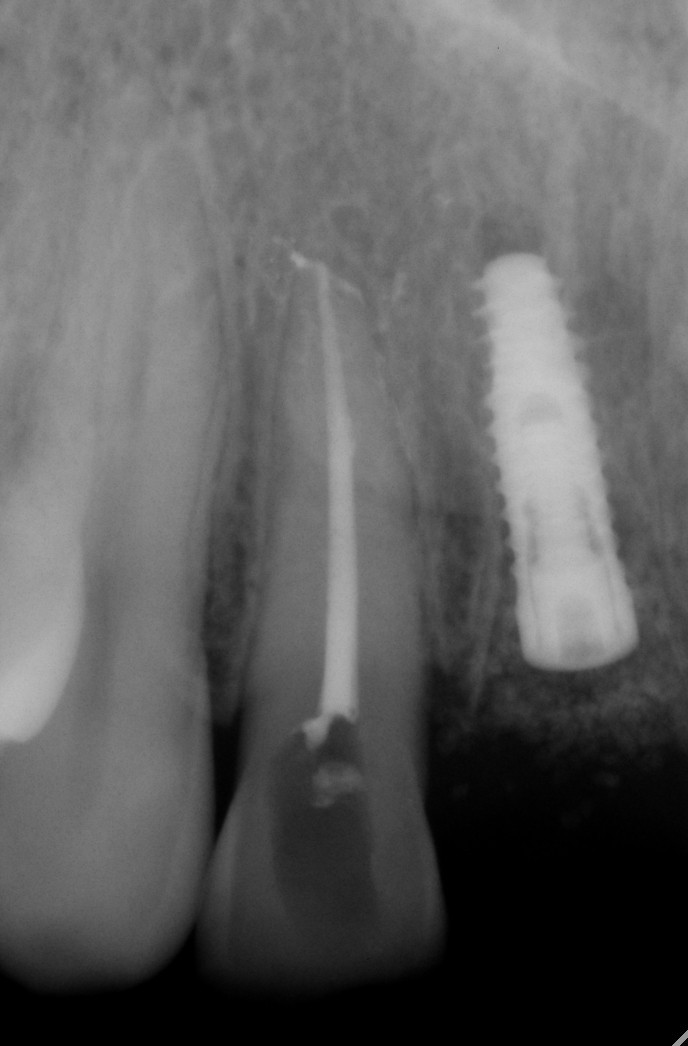

数字化根尖片